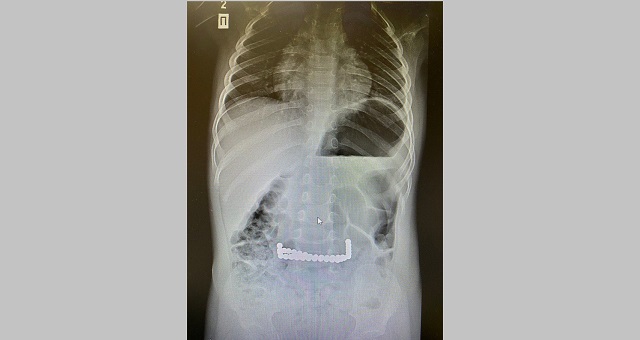

Правда ли, что магнитные шарики опасны для детей . . .

В Инстаграм распространяется видео, в котором заведующий хирургическим отделением Киевской детской больницы №2, главный детский хирург Киева Олег Доманский рассказывает об опасности, которую представляют для малышей конструкторы из магнитных шариков .